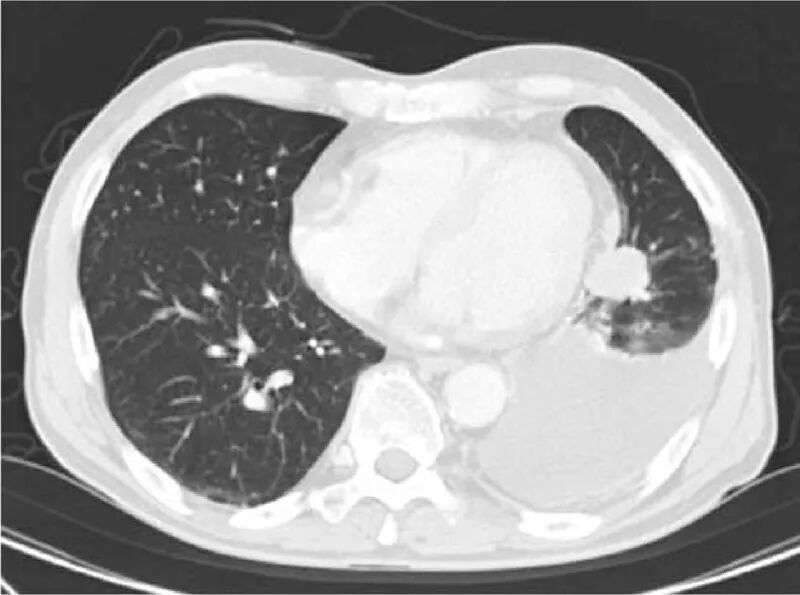

下面这张图是患者11年期间使用化疗和靶向治疗方案和服用时间的详细过程。